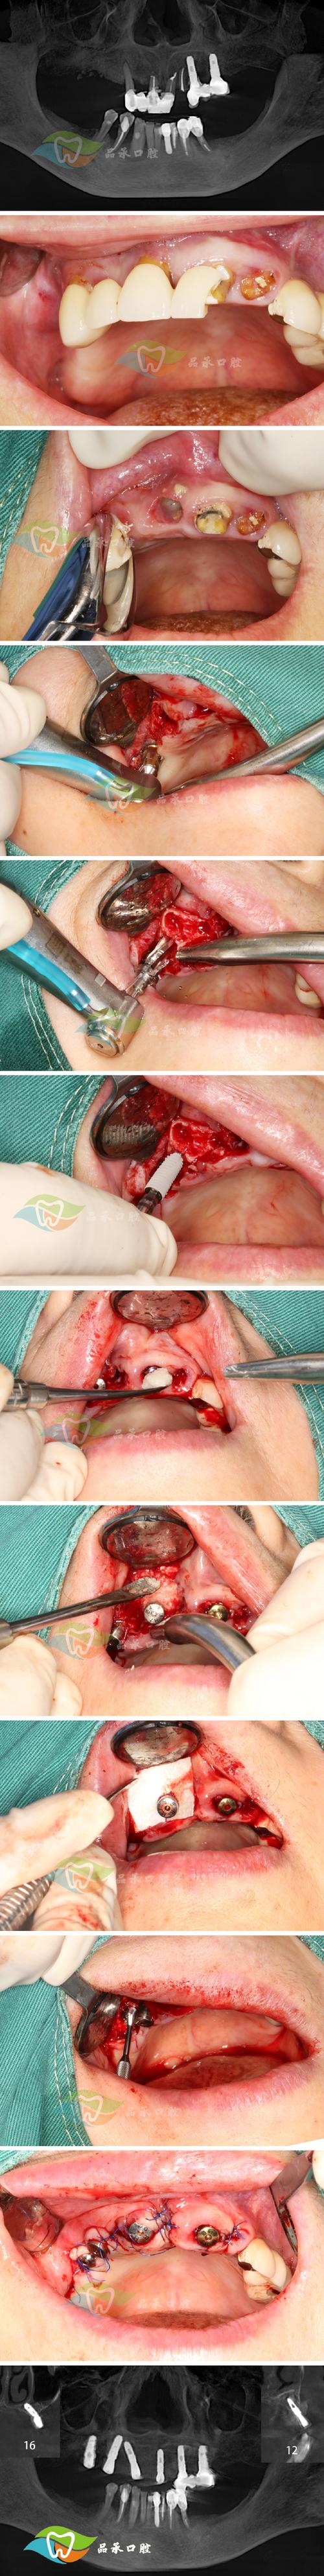

(图片来源网络,侵删)